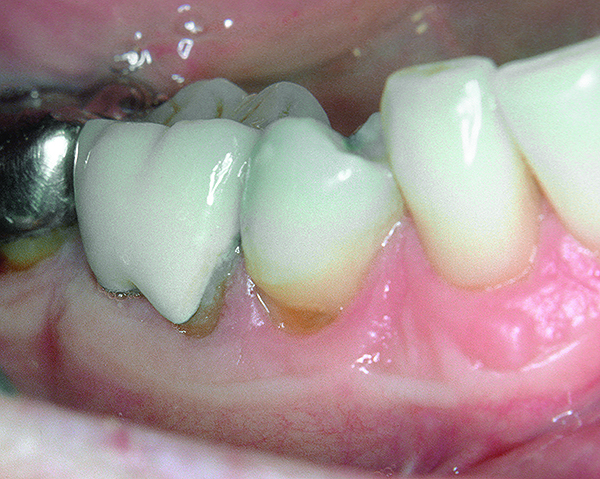

Fig 3. Bleeding on probing and increasing pocket depths around implant sites indicates a need for treatment.

Figure 3